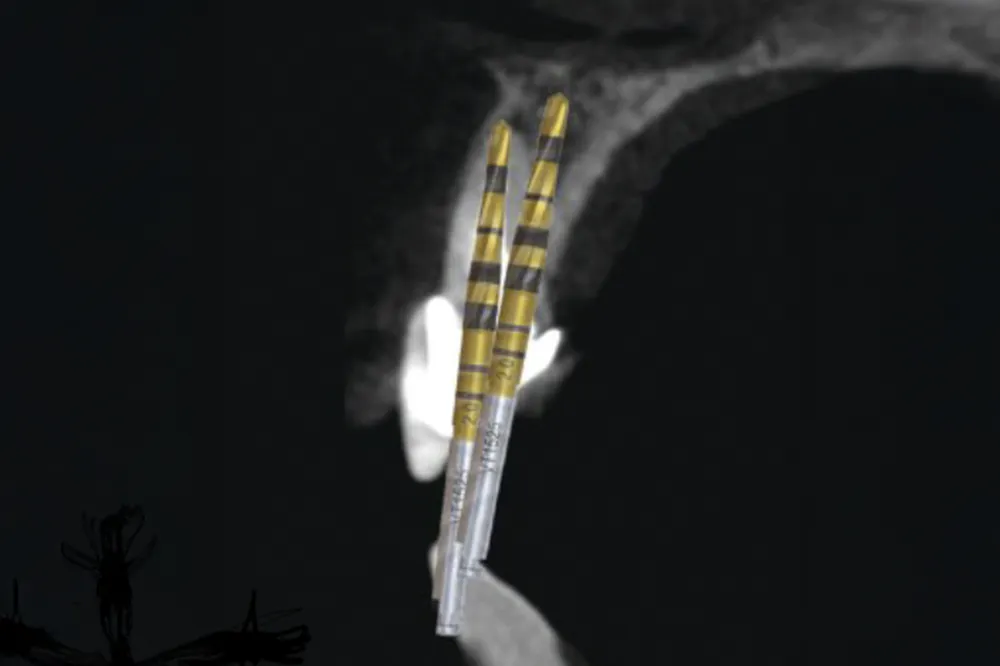

El uso de las fresas Densah® permite combinar la compactación ósea con una elevación hidráulica progresiva de la membrana de Schneider. El hueso compactado y, en su caso, los sustitutos óseos en forma de masilla como Novabone® Dental Putty (fosfosilicato de calcio) actúan como un pistón hidráulico que eleva suavemente la membrana, reduciendo el riesgo de desgarro y mejorando la experiencia del paciente.

Los estudios disponibles muestran tasas de perforación inferiores al 10% y tasas de éxito cercanas al 97%, incluso en casos con altura ósea residual limitada (figuras 3, 4, 5, 6 y 7).

Fig. 6. Secuencia de elevación sinusal cerrada. Elevación y compactación del biomaterial